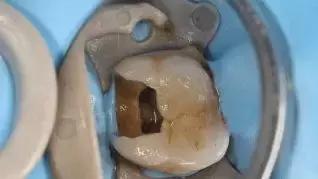

我们在补牙的时候,医生都会充分检查,进行腐坏处的清除再修复。出现后期疼痛是怎么回事?

2、一旦蛀牙越贴近牙髓,补完牙近期可能会受到充填材料刺激,牙髓被感染后,就不能再继续补牙了,这种情况远期通常是继发性龋并发牙髓炎,得重新去除材料再做根管治疗。

如果只是补牙修复的问题,一般可自行恢复,或持续无缓解可找补牙医生进行检查维护。如果检查出补过的牙齿继续感染,那就进行根管治疗吧~

反复说起的根管治疗怎么做?

先进行根管预备、进入牙髓腔,清理坏死的组织,测量牙齿长度,扩大根管,再将牙齿根管内的有机物的细小碎片和切削掉的硬组织类沾染源冲洗洁净,然后是根管消毒、用棉捻蘸一点醛和酚放置在根管内,进行次消毒,用封闭材质进行填充。